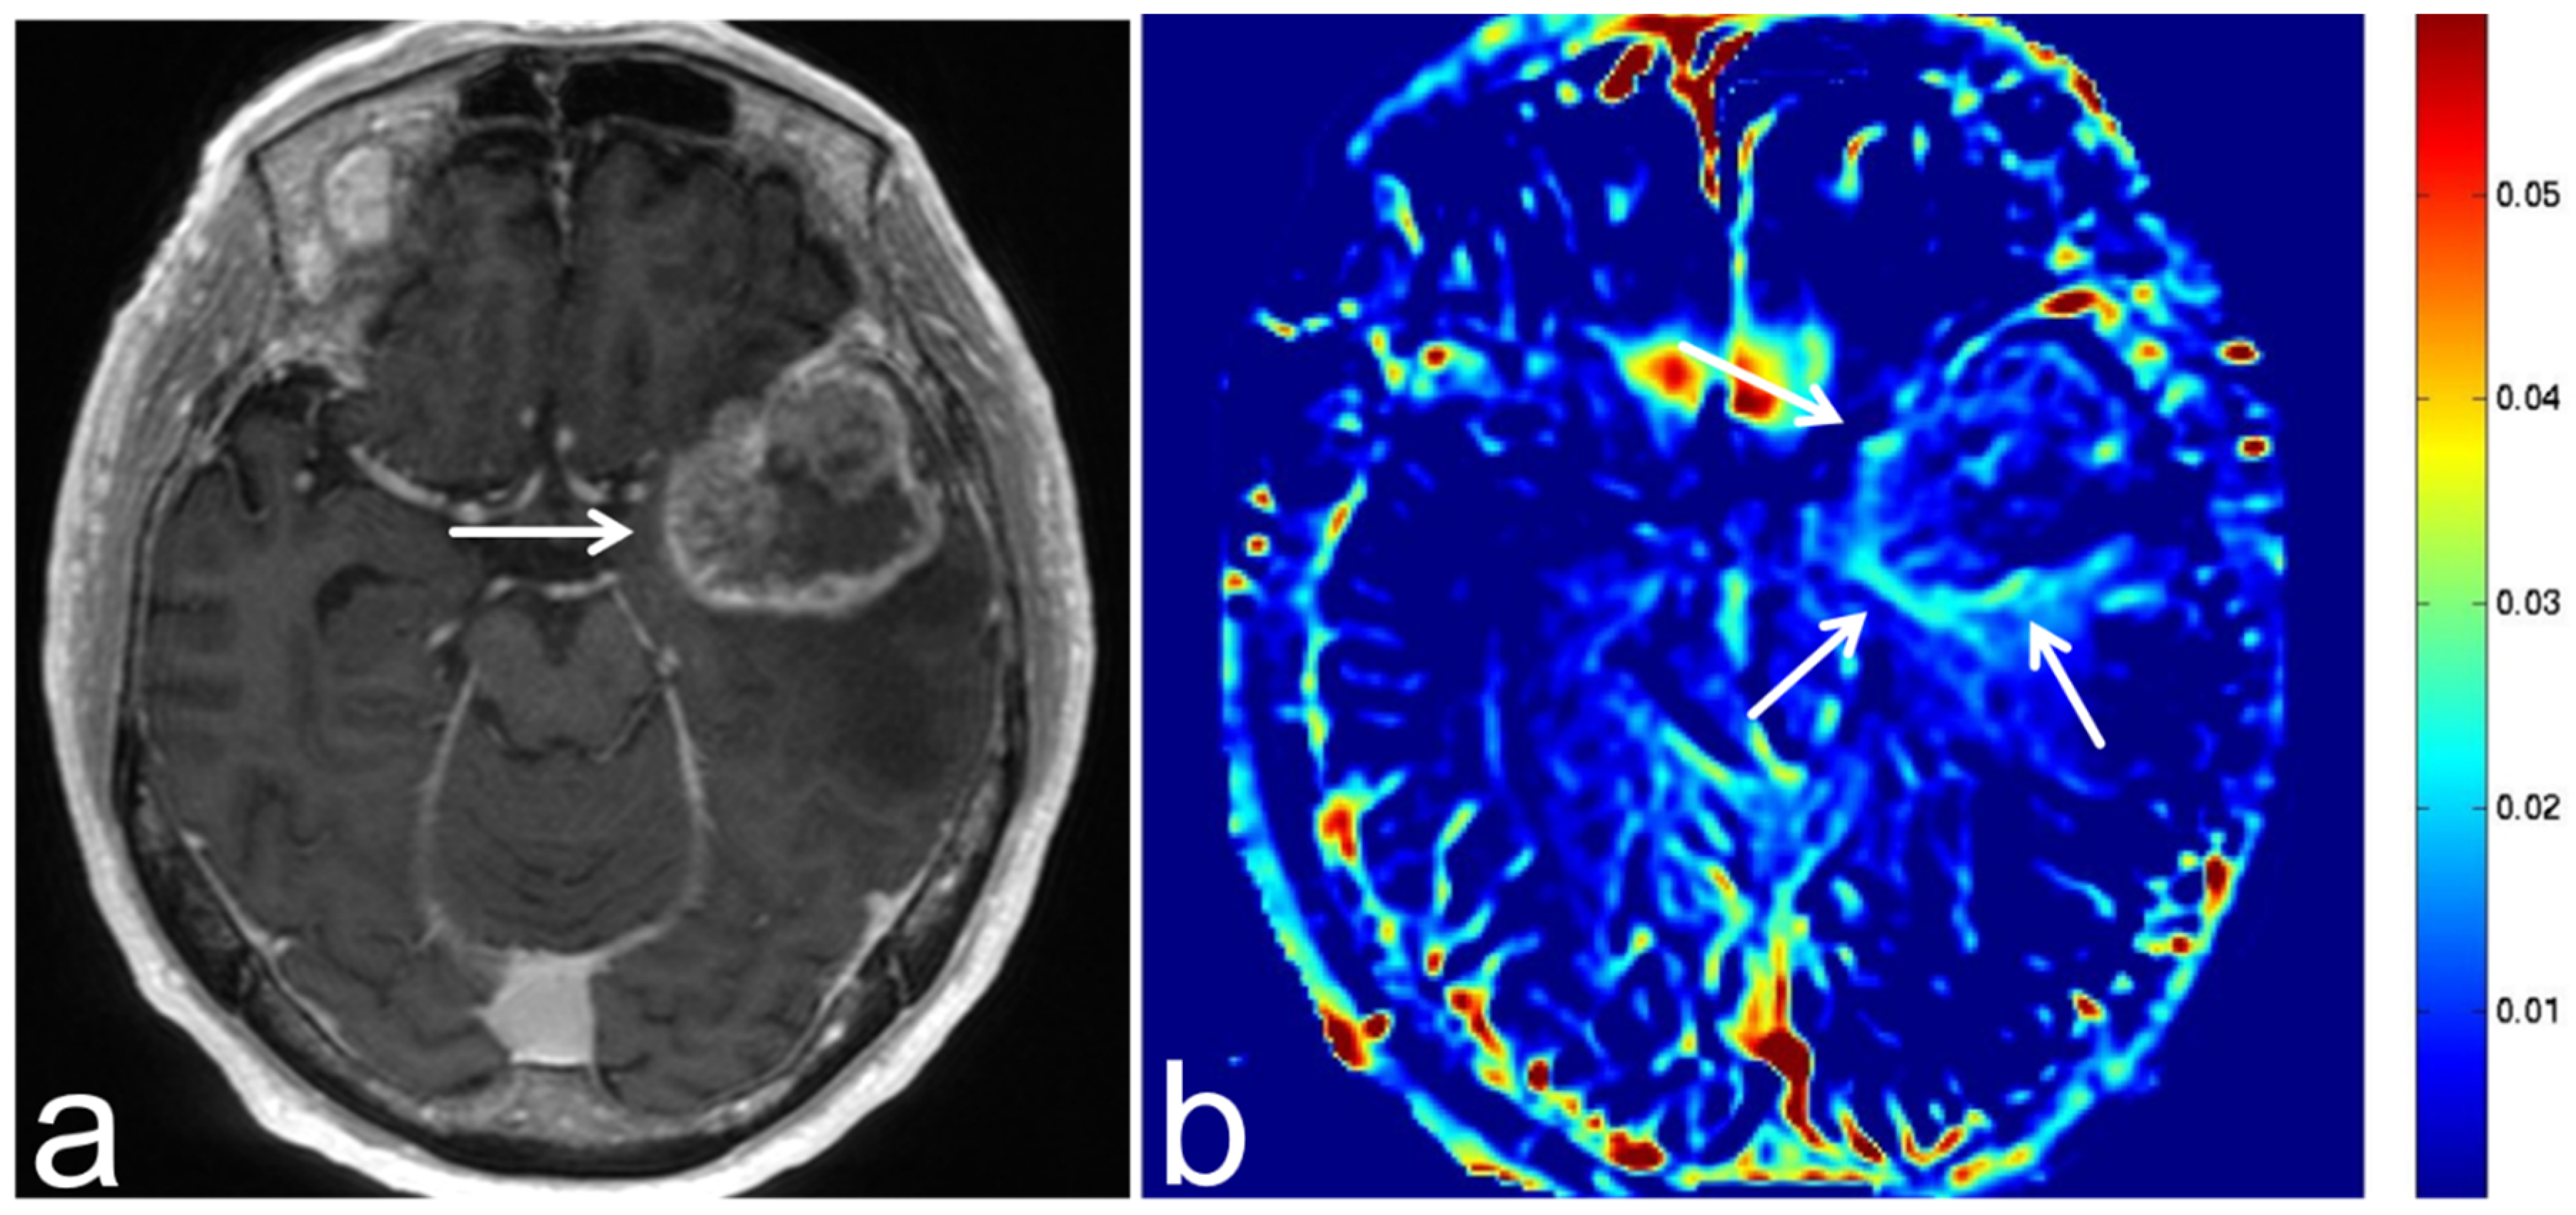

5.3. Glioblastoma

5.4. Malignant Lymphoma